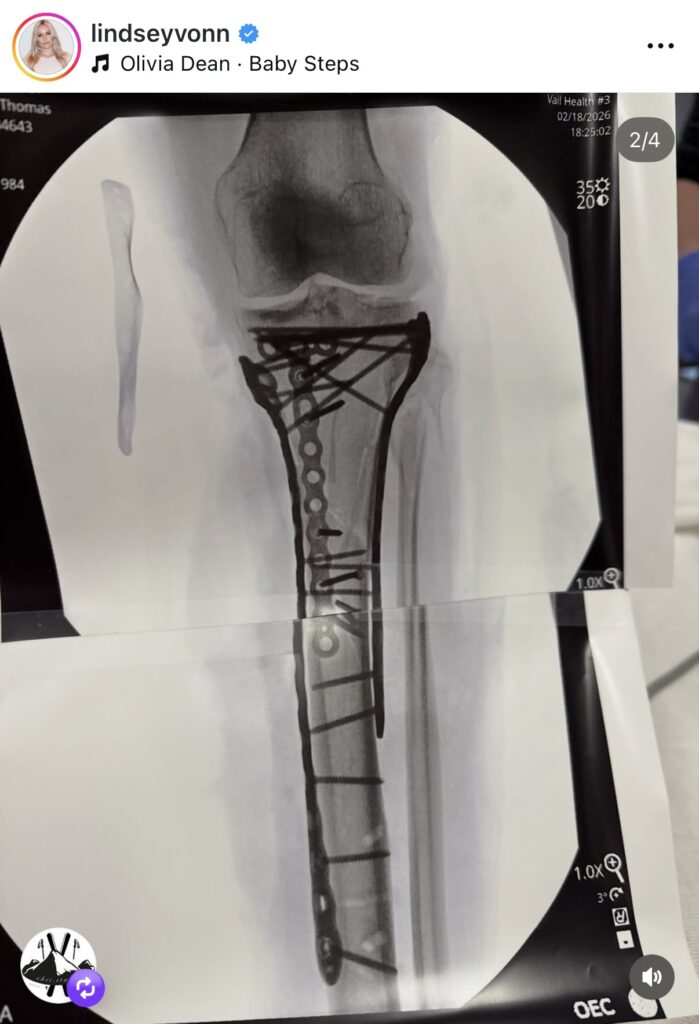

Vonn detailed the severity of her injuries, which included a complex tibia fracture along with fractures to her fibular head and tibial plateau. The trauma was further complicated by compartment syndrome, a serious condition caused by extreme swelling and internal pressure that can cut off blood flow and lead to permanent muscle and nerve damage if not treated immediately.

Dr. Tom Hackett performed an emergency fasciotomy to relieve the pressure in her leg, a procedure Vonn credits with saving her limb from amputation. She later underwent a six hour reconstructive surgery to rebuild her leg, which she said went amazingly well. In total, Vonn has had multiple procedures as doctors worked to stabilize and repair the extensive damage.